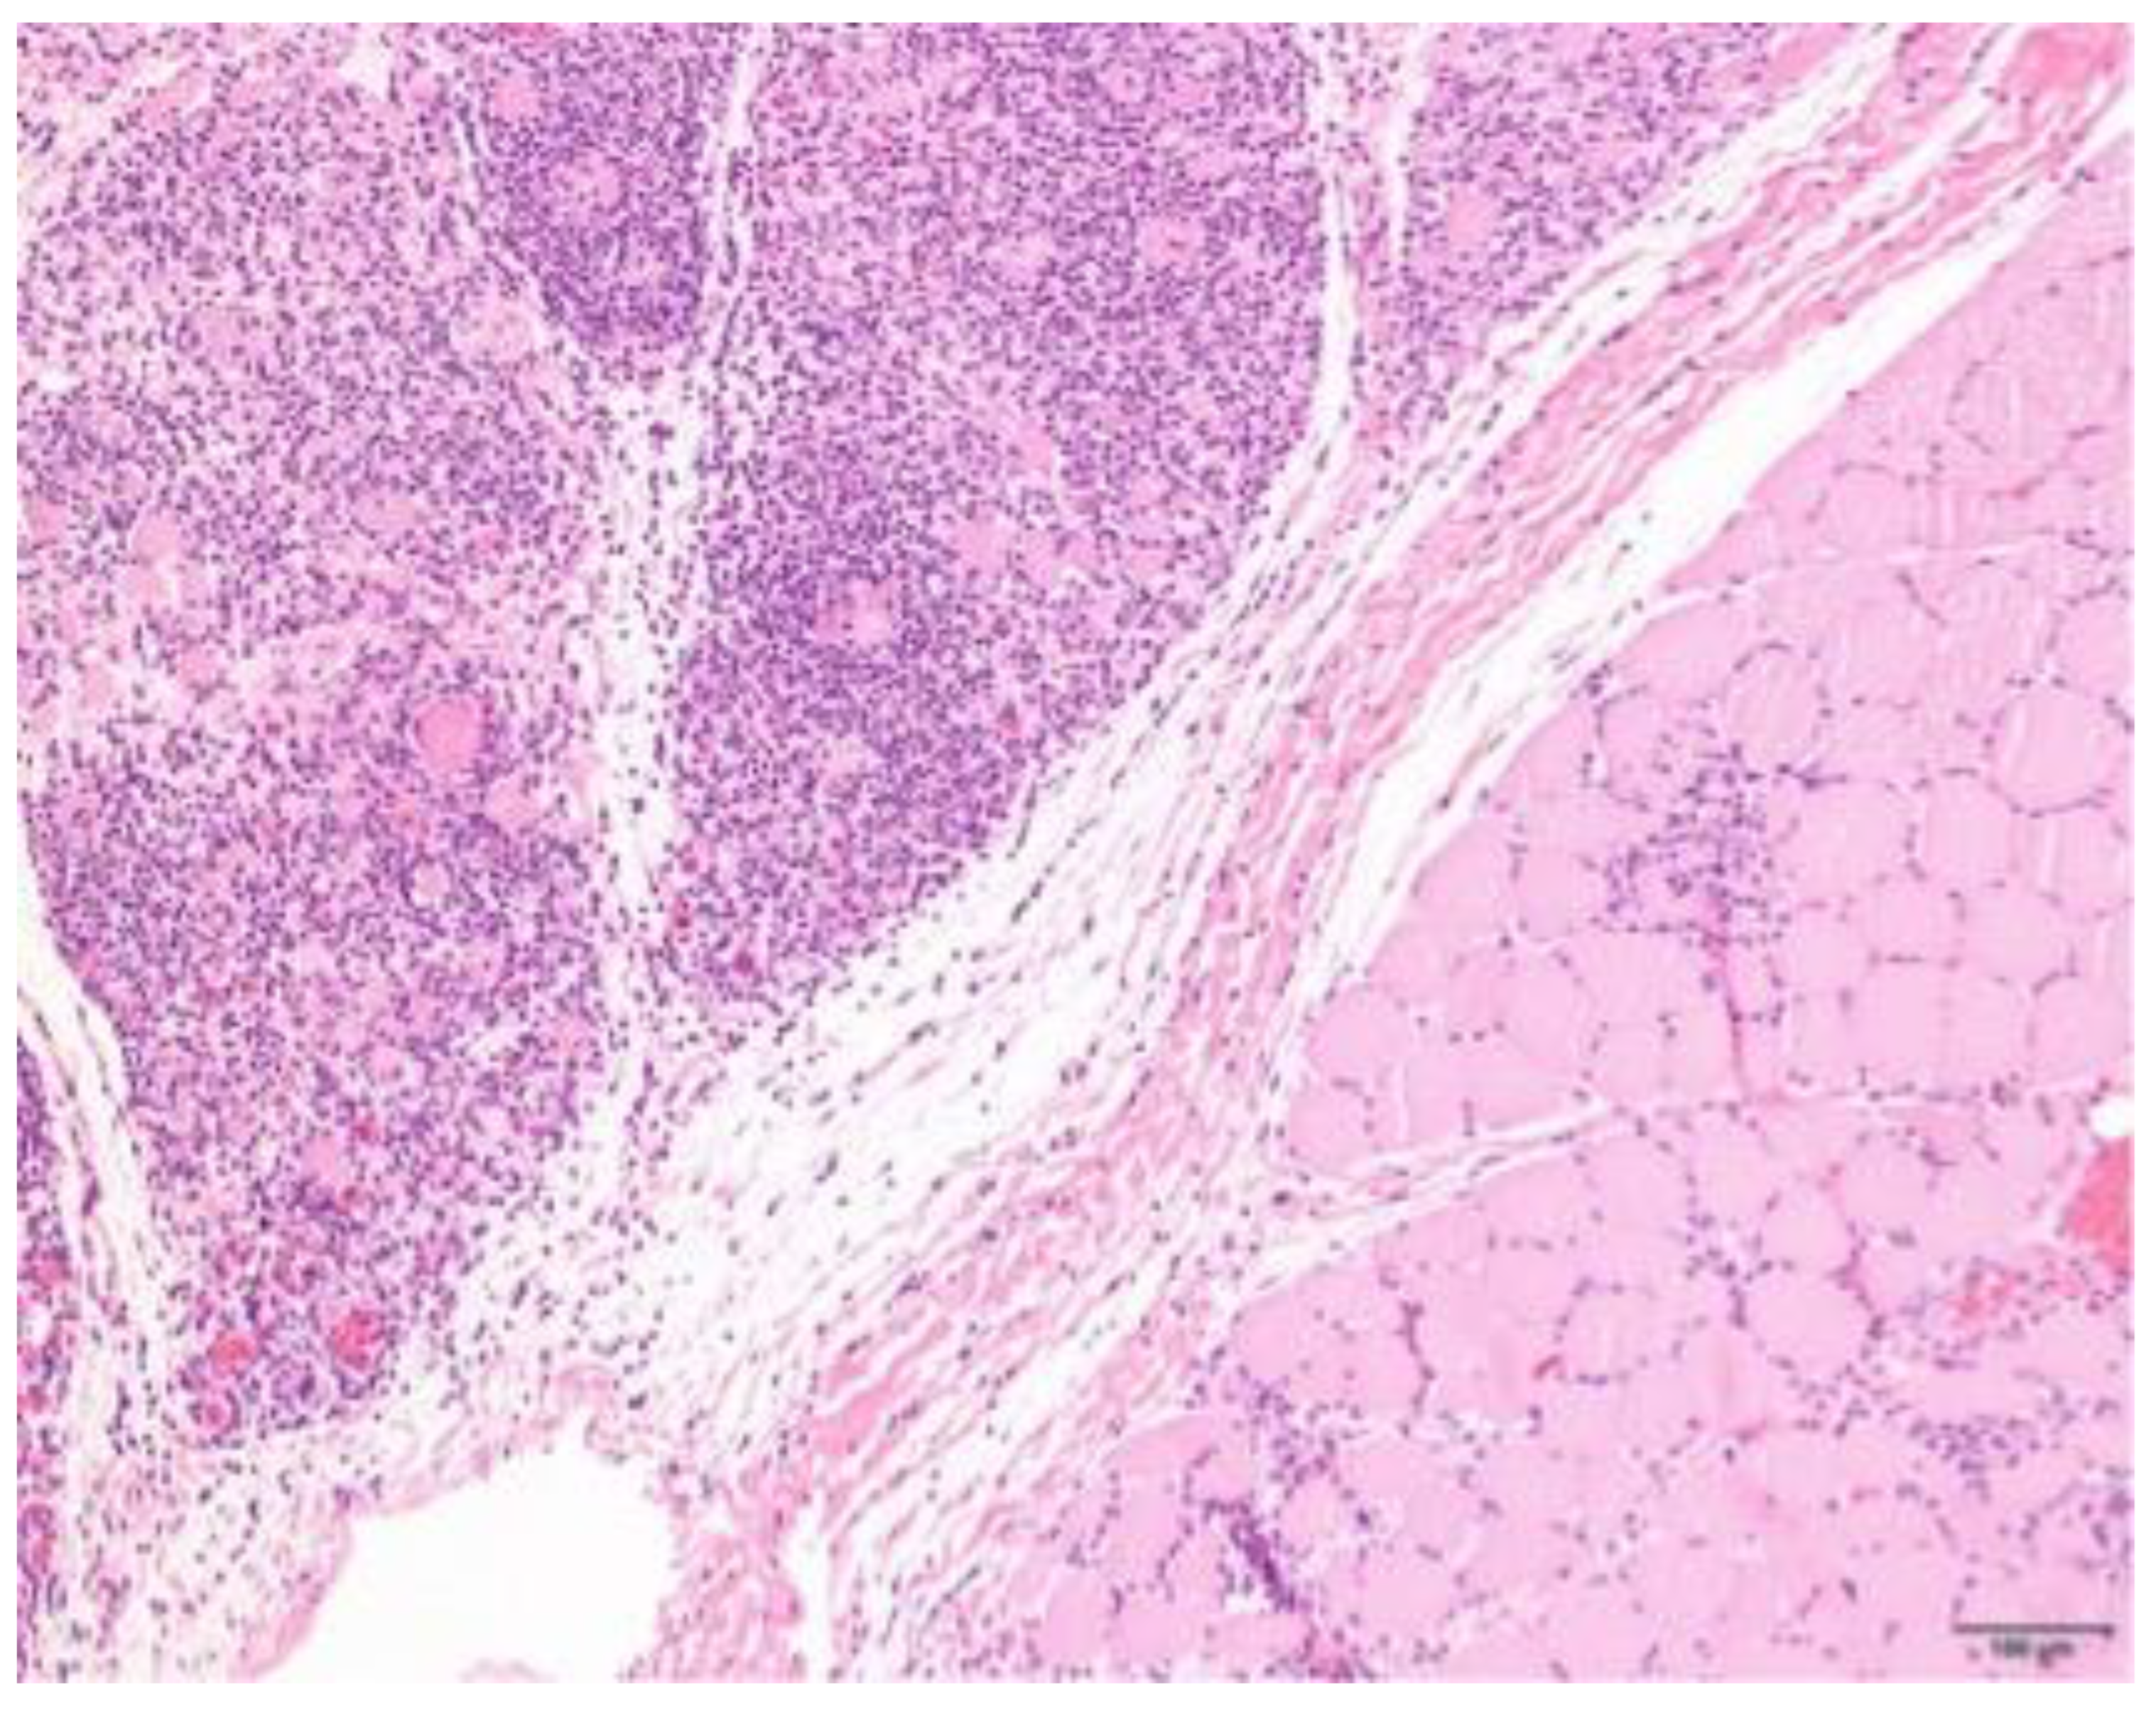

3.4. Histopathology

| Pattern | Expanse | Phase | Location Infiltrate | ||||||

|---|---|---|---|---|---|---|---|---|---|

| Focal | 2 | Mild | 5 | Subacute | 4 | Degeneration | 63 | Endomysium | 27 |

| Multifocal | 63 | Moderate | 13 | Chronic | 29 | Regeneration | 38 | Endomysium and perimysium | 17 |

| Severe | 9 | Atrophic | 25 | Perimysium | 5 | ||||

| Necrosis | 31 | ||||||||

| Fibrosis | 35 | ||||||||

| Characterization of Infiltrate and Severity | |||||||||

|---|---|---|---|---|---|---|---|---|---|

| Lymphocytes | Neutrophils | Eosinophils | Histiocytes | Plasmacells | |||||

| + | 18 | + | 25 | + | 22 | + | 16 | + | 22 |

| ++ | 29 | ++ | 10 | ++ | 8 | ++ | 28 | ++ | 14 |

| +++ | 22 | +++ | 4 | +++ | 6 | +++ | 31 | +++ | 5 |